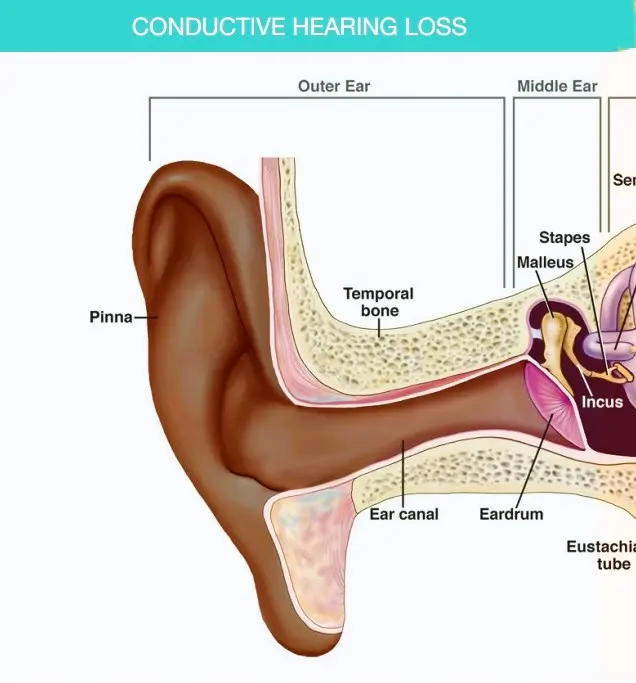

Conductive hearing loss happens when sound is unable to pass through the outer ear, ear canal, or middle ear to reach the inner ear. It may be caused by infections, fluid buildup, a perforated eardrum, or structural issues. This condition reduces sound volume, making soft or distant sounds harder to hear — but clarity remains unaffected

Conditions like infections or fluid buildup can often be treated with medication or minor surgical procedures such as grommet insertion.

Structural issues may be addressed through surgical intervention like tympanoplasty or ossicular reconstruction

Bone conduction hearing aids are particularly effective, as they bypass the problematic outer or middle ear and directly stimulate the inner ear.

Traditional hearing aids can amplify sounds to overcome the reduced transmission efficiency

Devices such as amplified telephones and FM systems can help individuals manage specific listening challenges in their daily lives

Regular hearing assessments ensure appropriate management of the condition over time